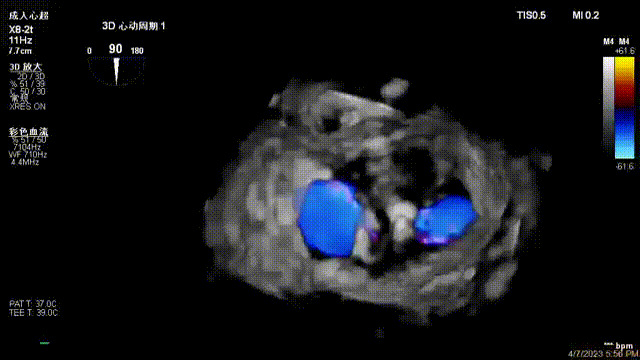

接受治療的是一例器質(zhì)性重度二尖瓣反流(DMR)患者,主訴“反復(fù)活動(dòng)后胸悶,氣促3年余”。術(shù)前超聲顯示,雙房增大,二尖瓣脫垂伴重度反流,輕度三尖瓣反流,輕度肺高壓,升主動(dòng)脈增寬。手術(shù)經(jīng)股靜脈-房間隔入路,采用全身麻醉插管,在TEE和DSA引導(dǎo)下完成房間隔穿刺。置入JensClip瓣膜夾系統(tǒng)后,在左房調(diào)整瓣膜夾的位置和軸向,后進(jìn)入左室,在TEE引導(dǎo)下捕捉二尖瓣前后瓣葉,并關(guān)閉瓣膜夾。經(jīng)TEE反復(fù)確認(rèn)手術(shù)效果后最終鎖定并釋放瓣膜夾。術(shù)后即刻超聲顯示瓣膜夾位置穩(wěn)定,功能良好,術(shù)前二尖瓣反流4+,術(shù)后0反流,肺靜脈逆流和左房壓都顯著好轉(zhuǎn),手術(shù)圓滿(mǎn)成功(以上數(shù)據(jù)都來(lái)源于醫(yī)院的臨床記錄)。術(shù)后患者狀態(tài)良好,目前已安排出院。

出院前隨訪(fǎng)超聲